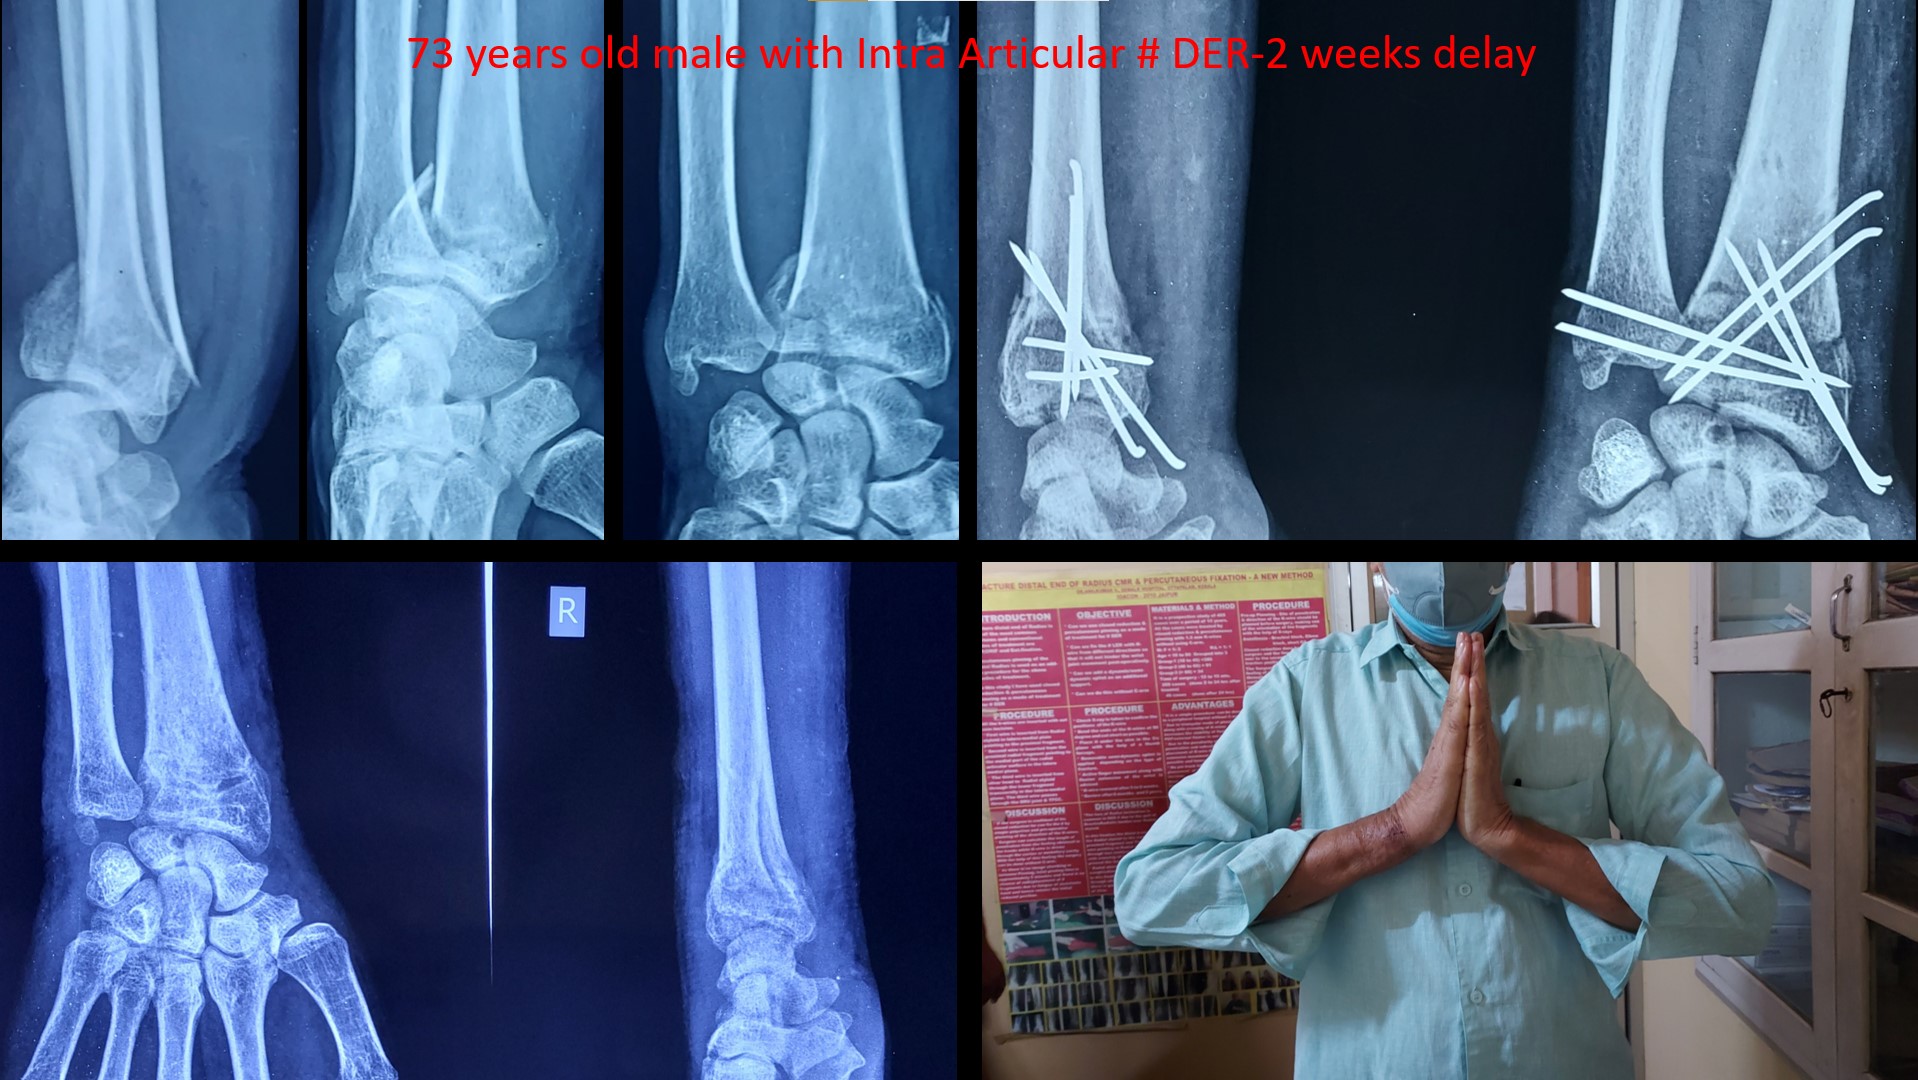

wrist